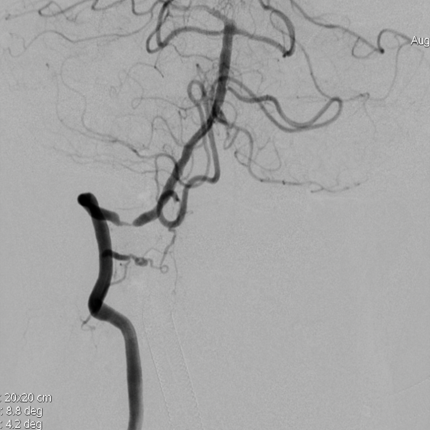

术后影像

术后即刻影像及患者术后情况:

造影见狭窄位置狭窄解除,支架贴壁良好,后循环各分支动脉显影良好。术后次日患者行走不稳情况明显改善,术后1月随访患者行走如常,未再发头晕。